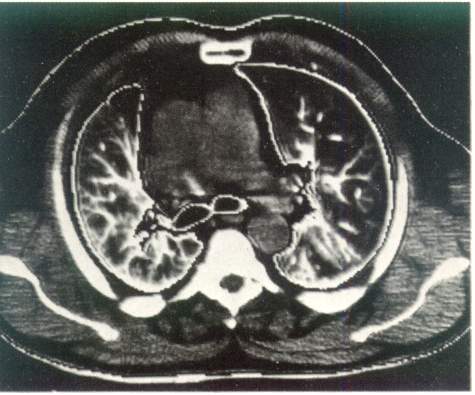

Рис. 3. Компьютерная томография органов грудной клетки. Норма.

Компьютерная томография дает возможность получить наиболее полную рентгенологическую информацию об опухолях и кистах средостения, сосудистых изменениях в легких, аневризмах, о состоянии трахеобронхиального дерева, характере и структуре «шаровидных образований в легких», патологических изменениях в плевре, грудной стенке, особенно при ее злокачественных поражениях (рис. 3).

В

озможности

рентгенологической диагностики заметно

расширились за счет становления и

клинического использования компьютерной

рентгенотомографии. По

сравнению с обычной рентгенографией

компьютерная рентгенография имеет в

десятки раз большую разрешающую

способность и позволяет различать ткани

с разностью по плотности до

0,5 %. Это дает возможность

четко определять границу между нормальной

и патологически измененной легочной

тканью. На компьютерных томограммах

органов грудной полости удается не

только локализовать патологический

очаг, но и определить его размеры, оценить

плотность и однородность, соотношение

с соседними анатомическими образованиями

и органами.